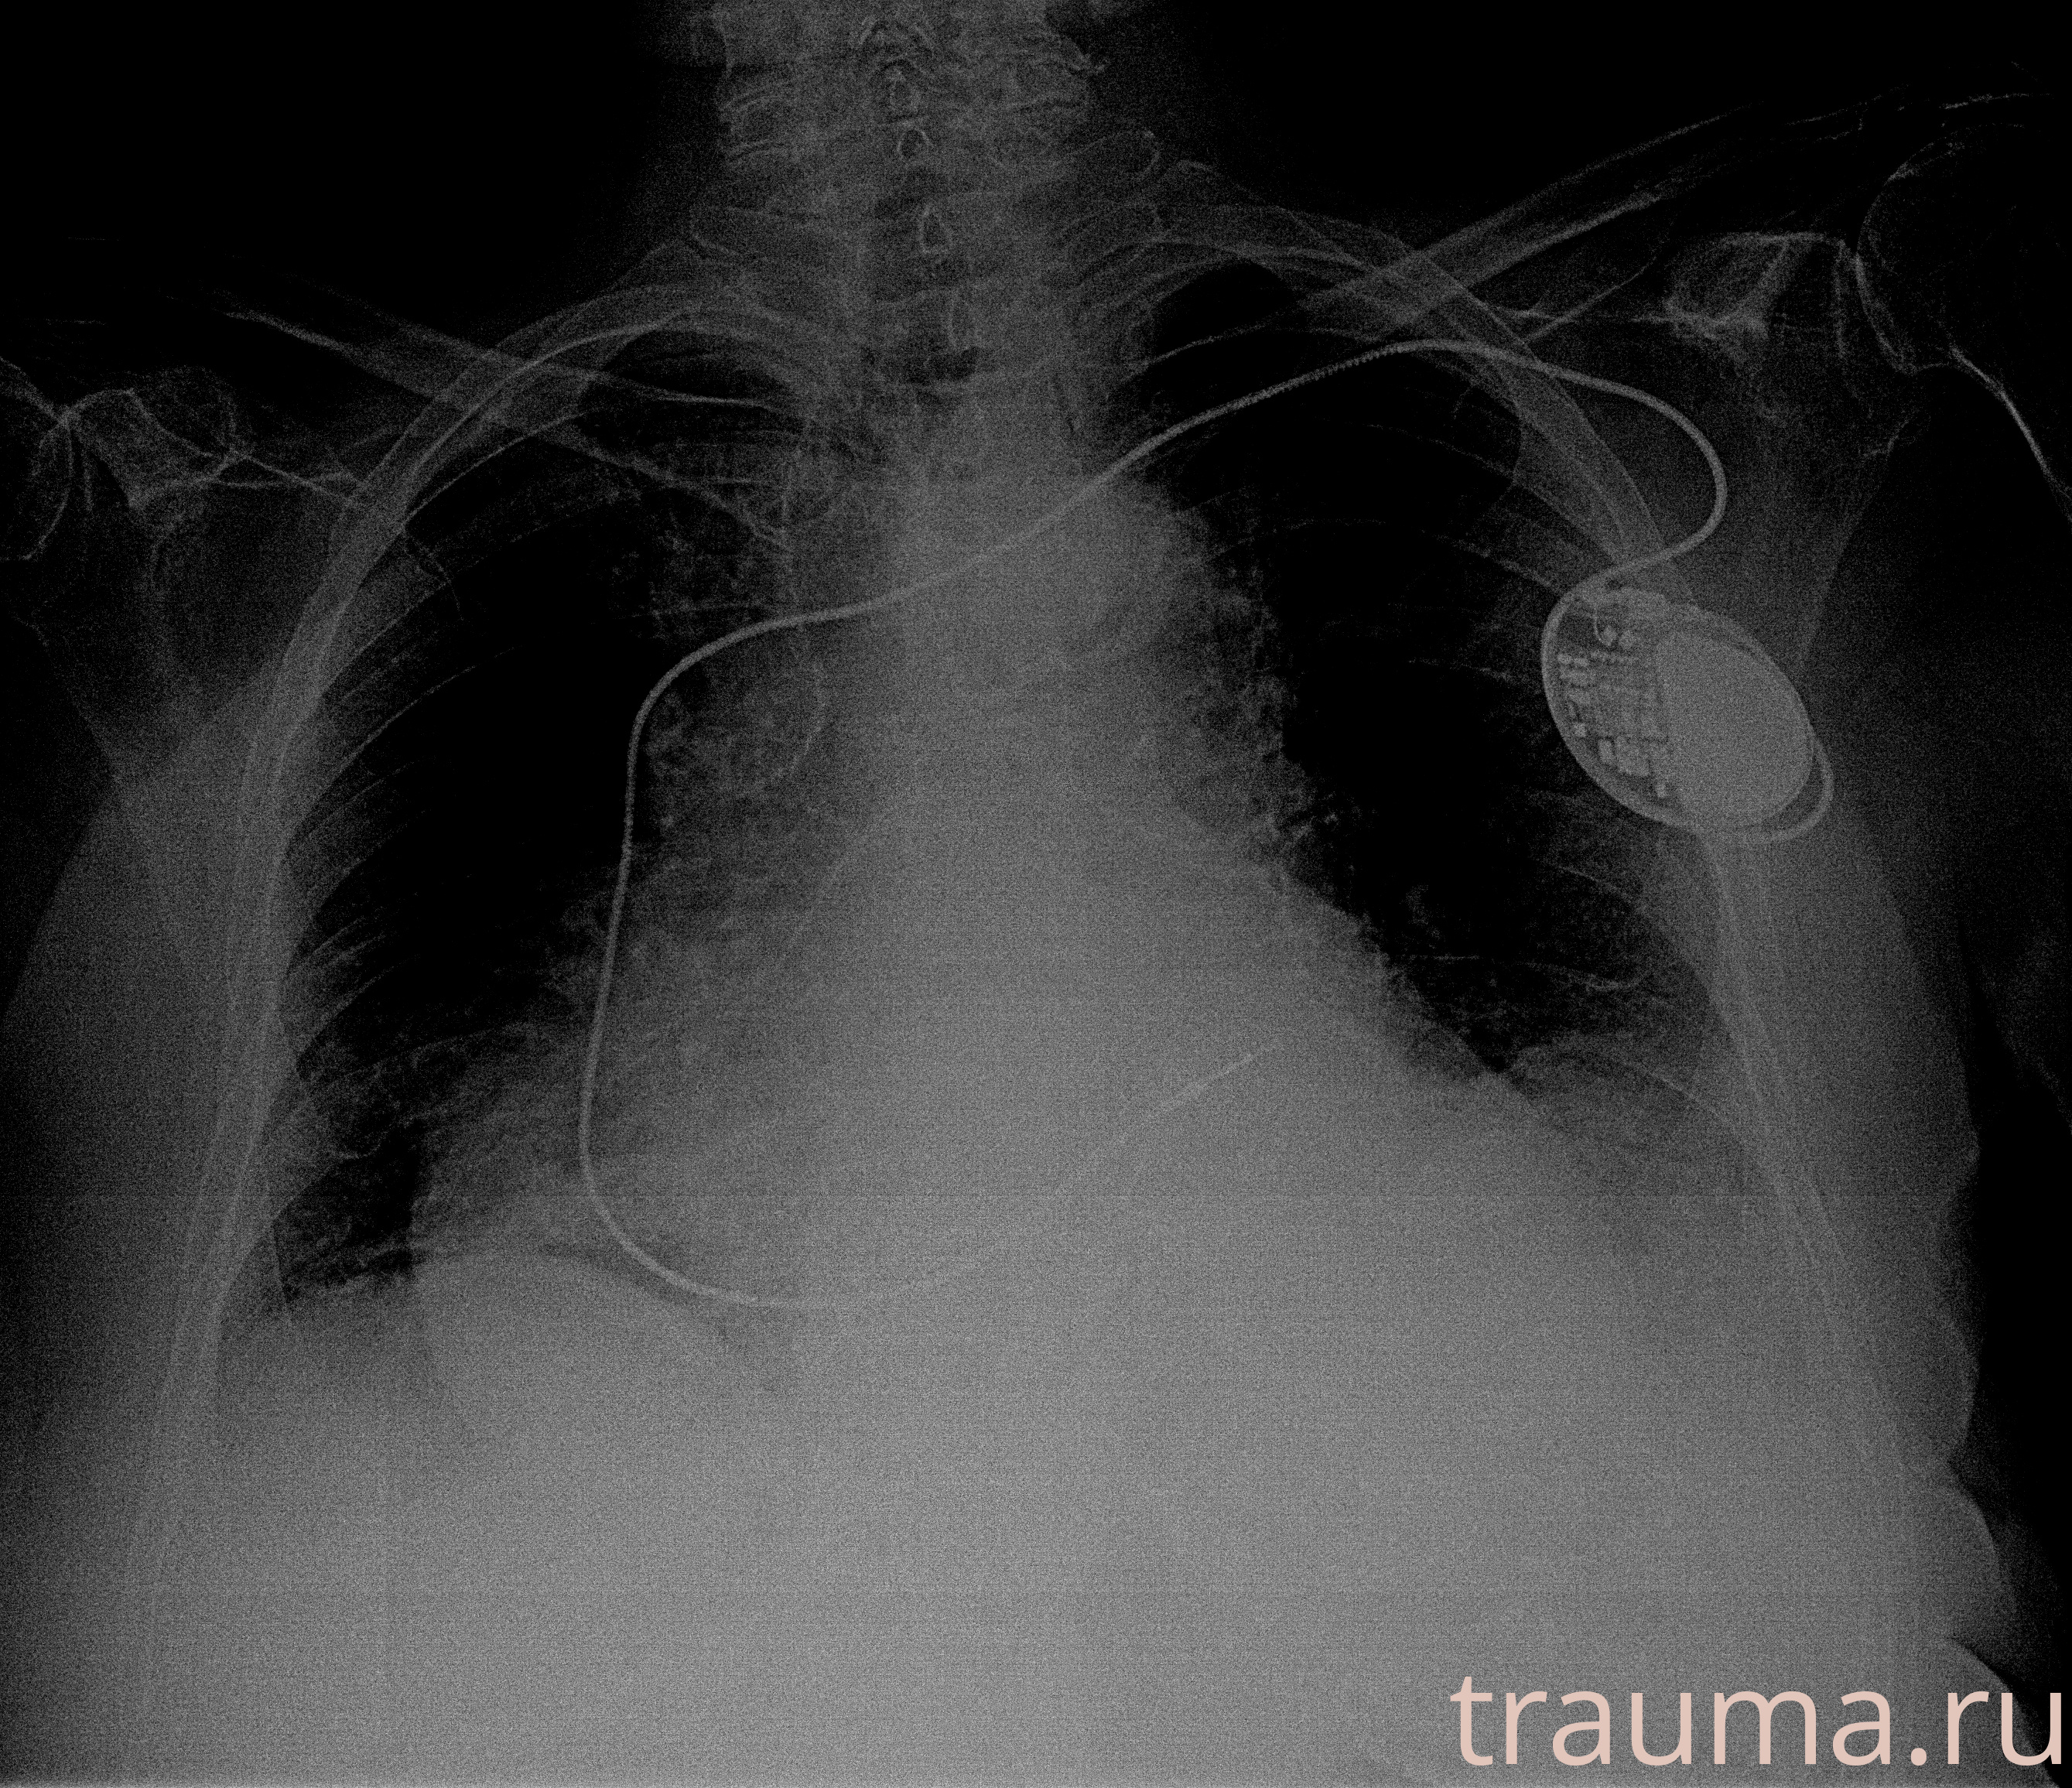

Рентгенограммы

Рентген на дому: по вашему адресу приезжает врач-рентгенолог, травматолог-ортопед с мобильным рентгеновским аппаратом, проводит диагностику травмы или заболевания, делает необходимые рентгенограммы, дает рекомендации по дальнейшему лечению. Получить качественные снимки в домашних условиях возможно благодаря уникальной методике, разработанной МосРентген Центром для института  Склифосовского

при переломе шейки бедра и пневмонии от компании МосРентген Центр - партнера Института имени Склифосовского